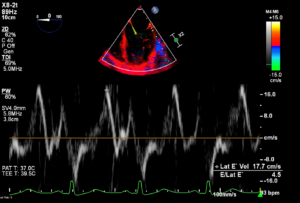

Mitral inflow and mitral TDI data are shown below

Findings are suggestive of: